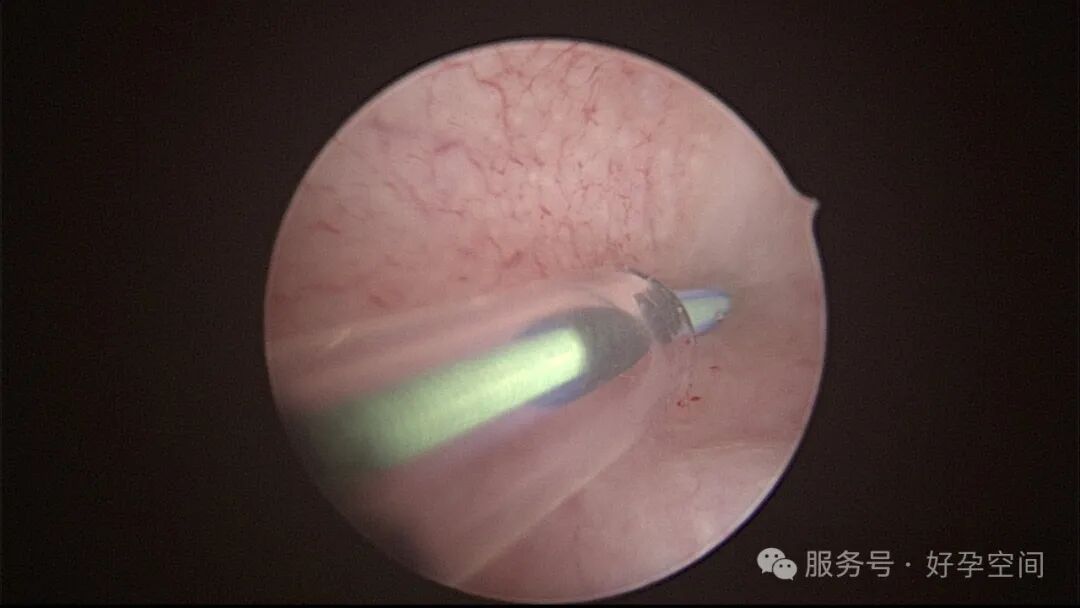

试管前宫腔镜检查